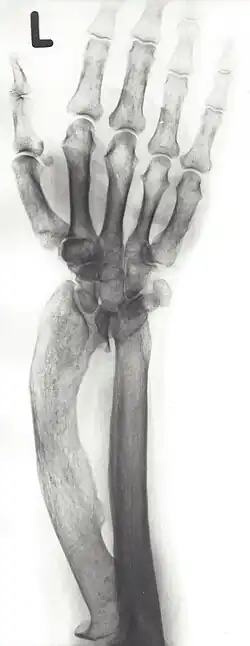

Madelung-Deformität

Die Madelung-Deformität ist eine Wachstumsstörung des Unterarms, die mit einer charakteristischen Fehlstellung einhergeht. Sie wurde erstmals umfassend 1878 von dem deutschen Chirurgen Otto Wilhelm Madelung beschrieben, nach dem auch die Madelungsche Handdeformität und der Madelungsche Fetthals benannt wurden. Allerdings gab es auch zuvor schon mindestens sechs Beschreibungen der Fehlstellung, u. a. von Guillaume Dupuytren.

Die Ulna ragt an der Dorsalseite des Handgelenks hervor und die Speiche ist weitbogig nach volar und ulnar verbogen. Dadurch kommt es zur sogenannten Bajonett-Fehlstellung der Hand mit Subluxation der Handwurzel.

In Röntgenaufnahmen des Handgelenks zeigt sich eine starke Schiefstellung der distalen Radiusgelenkfläche, die nach ulnar und volar verkippt ist. Die Elle ist überlang (Ulna-plus-Variante) Der Spalt zwischen Speiche und Elle kann stark vergrößert sein und keilförmig aussehen (engl. chevron carpus) sein, so dass das Mondbein hineinrutscht und keilförmig verformt wird. Die übrigen Handwurzelknochen liegen subluxiert volarseitig. Sehr selten gibt es auch eine inverse Madelung-Deformität, bei der die Speiche nach dorsal statt volar verbogen ist und die proximale Handwurzelreihe handrückenseitig subluxiert.

- ↑ Röntgenbild des rechten Unterarms